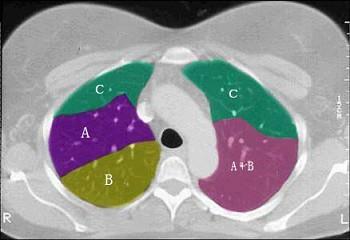

结合肺段模式(见图),选出右肺下叶的组成 ( )A.FB.F+GC.F+G+HD.F+G+H+IE.F+G+H+I+J

问题 结合肺段模式(见图),选出右肺下叶的组成 ( )

选项 A.F B.F+G C.F+G+H D.F+G+H+I E.F+G+H+I+J

答案 E